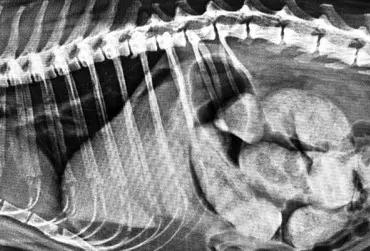

Zarażenie psa pasożytem nicieniem Dirofilaria immitis – opis przypadku

W artykule opisano przypadek dirofilariozy u psa wywołanej D. immitis. U badanego pacjenta stwierdzono patognomiczny obraz zmian w badaniu rentgenowskim i ultrasonograficznym układu sercowo-naczyniowego.